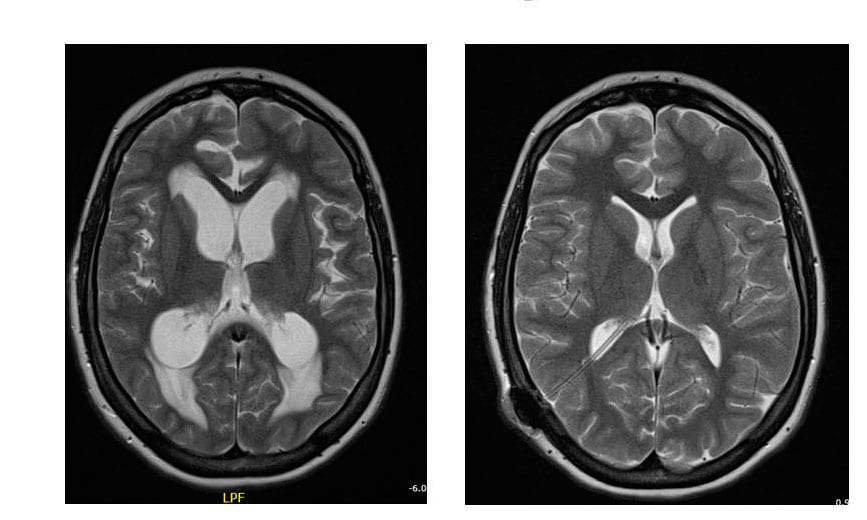

MRI-foto van waterhoofd. Bron: kinderneurologie.eu.

MRI-foto’s van waterhoofd: links voor drainplaatsing en rechts na drainplaatsing. Bron: kinderneurologie.eu.

Om schade aan de hersenen te voorkomen, is een snelle diagnose en behandeling belangrijk. Is er een vermoeden dat je (ongeboren) baby een waterhoofd heeft, dan kan er een diagnose worden gesteld door middel van de 20-wekenecho, een CT-scan van het hoofd of een MRI-scan. Er wordt dan gekeken naar de grootte van de hersenkamers. Normaal gesproken zit er zo’n 150 milliliter vocht in de hersenkamer en rond de hersenen. Op een CT-scan worden de hersenen licht grijs weergegeven en is het vocht in de hersenen zwart aangegeven. Te veel zwart duidt op te veel vocht in de hersenen en dus op een waterhoofd.